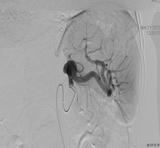

近日,我院介入科成功完成了首例脾主干动脉瘤栓塞术,填补了介入科在内脏动脉瘤介入治疗领域的空白,为我院三级医院创建、介入科技术能力建设与发展提供了重要的能力支撑。 41岁的马女士,因体检发现脾动脉瘤入住我院普外科。普外科邀请介入科赵蔚主任会诊,结合患者脾动脉瘤重建图像,赵主任建议行DSA引导下动脉瘤内微...2022-12-16